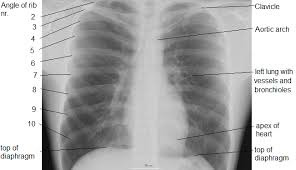

Each of these anatomical structures should be viewed using a systematic approach. Xray is a type of radiography and most widely used investigation. In this article we will focus on: Many clinical conditions can be evaluated by this simple radiology test. L the portion of the left lung that corresponds anatomically to the right middle lobe is incorporated into the left upper lobe. Labeled chest radiographs teaching radiologic anatomy with a level of detail appropriate for medical students. Both lungs should be well expanded and similar in volume. In fact every radiologst should be an expert in chest film reading.

Labeled chest radiographs teaching radiologic anatomy with a level of detail appropriate for medical students. • the straight back syndrome or pectus. You have completed this module. The interpretation of a chest film requires the understanding of basic principles. L the portion of the left lung that corresponds anatomically to the right middle lobe is incorporated into the left upper lobe. Living anatomy of the chest for 1st year medical students original version compiled by dr. It first appears too complicated to read the chest xrays because we barely know what. Is there any inhaled foreign body? L these two lobes are separated by a major fissure, identical to that seen on the right side, although often slightly more inferior in location. © 2011 john wiley & sons, ltd. Patterns in 21st century lung infections. Abcde aproach the anatomy of the heart can appear artificially larger due to this image orientation. Published 2011 by blackwell publishing ltd.

Evaluation of a chest radiograph may appear to be simple, but is in fact a complex task requiring careful observation, sound understanding of chest anatomy, and knowledge of the principles of physiology and pathology. Major structures are shown in fig. However, finding problems that are often a/w arrhythmias, such as cardiac enlargement and lung disease, should alter one to the possibility of arrhythmias. The interpretation of a chest film requires the understanding of basic principles. Conclusion of living anatomy of the chest congratulations!